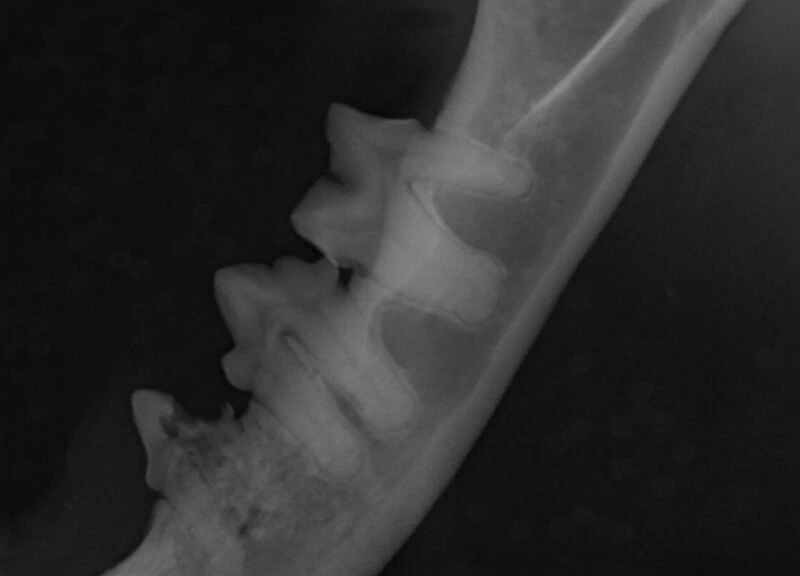

A relaxed and interactive online learning session focused on improving confidence in interpreting dental radiographs in small animal practice.

Each session will review real clinical cases, discussing radiographic findings, common pitfalls, and practical tips for everyday dentistry. We will also include discussion of evidence-based treatment options and clinical decision making.